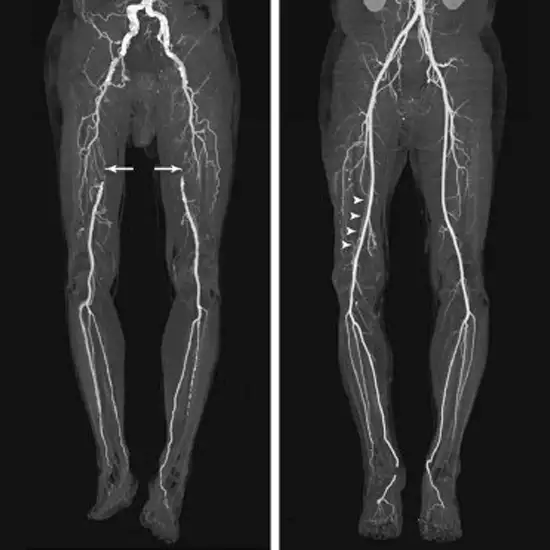

CT Angiography Arteries Lower Limb is an imaging scan that is used to evaluate the arteries system of the lower limb. This scan is performed on patients with peripheral artery diseases. To perform this scan, contrast media is injected into the patient. Contrast media highlights the narrowed or blocked arteries and it becomes easy for a doctor to detect the problems easily.

CT Angiography artery Lower Limb is a diagnostic imaging technique that is used to visualise the arterial structures of the lower limb. The diagnostic scan is used to examine the arteries flow in your lower limbs. The test uses a special contrast media that is given to you through the intravenous route to help clearly visualise the arteries. This test is generally performed in cases where the patient has peripheral arterial disease or other problems.

It is used to determine and detect

• Any narrowed or blocked arteries of the legs including knee, ankle, pelvis, etc.

• The injured blood vessels

• Abnormalities of veins that may form a blood clot.

• The peripheral artery disease.

• Any swollen artery in the legs, decreasing the blood flow.

• The fat deposition in the artery walls